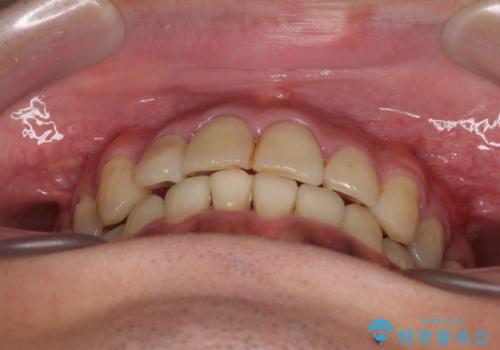

第二小臼歯抜歯の矯正治療は、治療期間が長引くことが多いですが、動きが非常に良く、予定の治療期間で終えることができました。

上下の正中も思っていた以上に良い位置に改善されました。